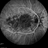

Persistent Placoid Maculopathy

placoid, maculopathy

68-year-old woman with decreased central vision over past few months following viral illness.